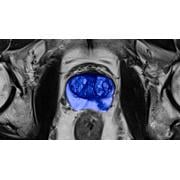

Personalized medical care conjures an image of exactness. Precision. Its realization was once believed attainable through sequencing the human genome…

Effective screening may be the key to America’s future. Only by catching disease early, before disease can injure the patient and impose financial…

Cancer screening is the only circumstance in which apparently healthy people subject themselves purposely to an agent known to cause cancer. It is…